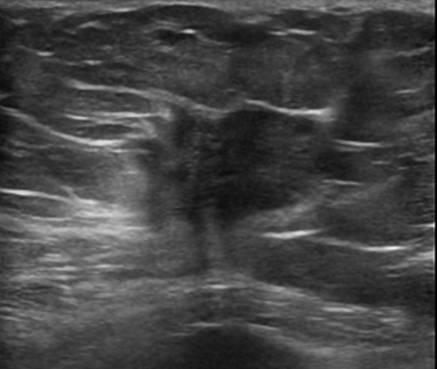

Ung thư vú - Ảnh 4

Ung thư vú

» Thông tin: Nữ giới – 72 tuổi.

» Lâm sàng: Khối tuyến vú.